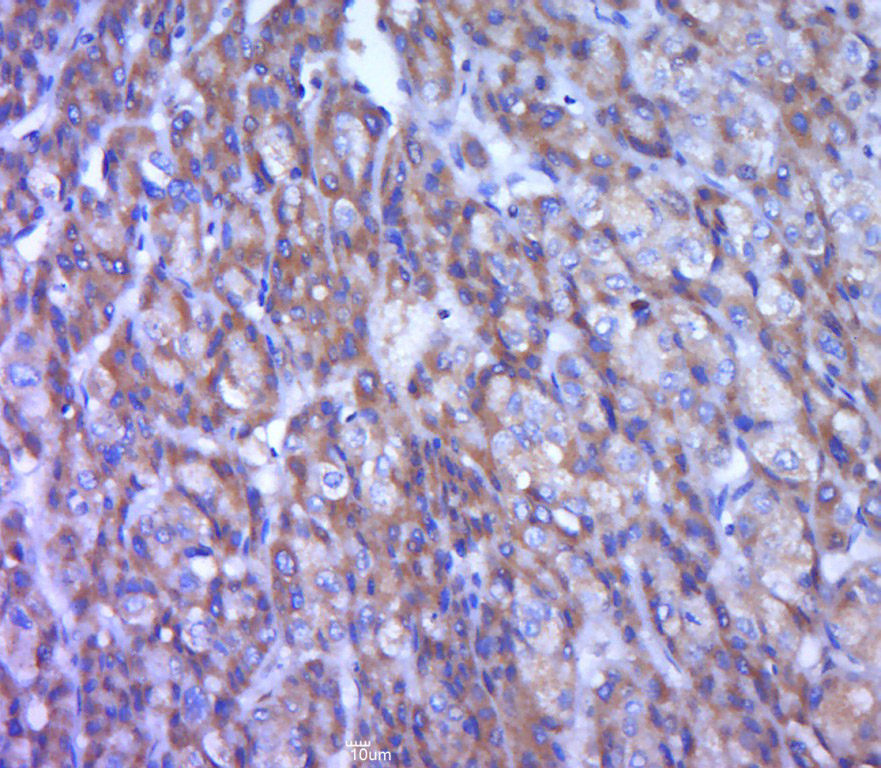

| 英文名称 | TREM1 Rabbit pAb |

| 中文名称 | 髓系细胞触发受体1抗体 |

| 产品应用 | WB=1:500-2000, IHC-P=1:100-500, IHC-F=1:100-500, IF=1:100-500, Flow-Cyt=1μg/Test Not yet tested in other applications. |

| {IHC-P} | {1:100-500} |

Primary: Anti-TREM1 (bs-10306R) at 1/300 dilution